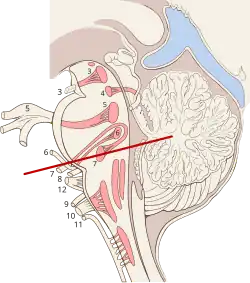

Der Nucleus nervi abducentis (Syn. Nucleus motorius nervi abducentis, Abduzenskern) ist ein beidseits vorhandenes Kerngebiet (Nucleus) in der Brückenhaube, von dem der Nervus abducens (Hirnnerv VI) ausgeht. Er gehört mit dem Nucleus nervi oculomotorii, dem Edinger-Westphal-Kern und dem Nucleus nervi trochlearis zu den Augenmuskelkernen, die über das mediale Längsbündel (Fasciculus longitudinalis medialis) miteinander verbunden sind.

Der Nucleus nervi abducentis liegt im Hirnstamm im Bereich der Rautengrube am Boden des vierten Hirnventrikels. Er wölbt, zusammen mit dem inneren Knie des Nervus facialis, den rostralen Boden der Rautengrube leicht vor (Colliculus facialis).

Die cholinergen Efferenzen des Nucleus nervi abducentis ziehen an der Basis des Hirnstamms als Nervus abducens zum gleichseitigen (ipsilateralen) Musculus rectus lateralis. Darüber hinaus gibt es kreuzende glutamerge Neurone zum Nucleus nervi abducentis der Gegenseite, die kontralateral zum Nucleus nervi oculomotorii aufsteigen und monosynaptisch an den Nervenzellen für den Musculus rectus medialis enden. Schließlich gibt es Projektionen zum Flocculus des Kleinhirns.